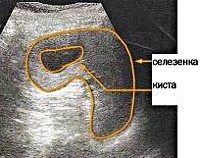

D73.4 Киста селезенки